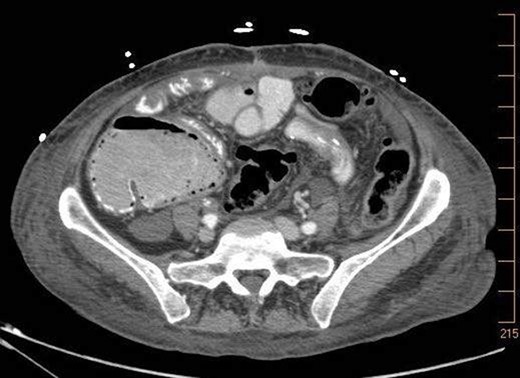

A 57-year-old non-toxic appearing female with a medical history of diverticulosis and malnutrition, and a surgical history significant for small bowel obstruction due to jejunal lymphangioma status post exploratory laparotomy and resection of bowel (2.2018). This patient presents with epigastric pain ×2 days with radiation to left upper quadrant and nausea with emesis, concerning for obstruction. In the Emergency Department, the patient was non-toxic appearing, hemodynamically stable, with no leukocytosis (7.4), or elevated lactic acid (1.2). Imaging, XR (Fig. 1) and CTAP (Fig. 2), demonstrating SBO with free air concern for perforated viscus. The concern for free air on imaging, in the setting of abdominal pain with symptoms of obstruction, mandated an operative intervention. On 7.5.18 the patient underwent exploratory laparotomy and was found to have emphysema of proximal jejunum, and underwent 125 cm resection of jejunum (Figs 3 and 4). Pathology of the specimen demonstrated multiple air filled cystic serosal nodules consistent with PCI (Figs 3 and 4, Supplementary Fig. S7).

7.4.18:CTAP w/IV and PO contrast: suggestive for small bowel obstruction, distal small bowel collapsed, mild or moderate free air suggestive of perforated viscus, free fluid in dependent portion of pelvis.